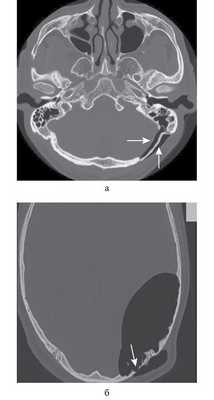

Рис. 1. КТ височных костей пациентки М. а — коронарная проекция: деструктивная полость в пирамиде височной кости, заполненная субстратом неоднородной плотности, капсула лабиринта значительно разрушена на уровне базального и апикального завитков улитки, латерального и верхнего полукружных каналов; б — аксиальная проекция: деструктивная полость с разрушением задней грани пирамиды, передневерхней и нижней поверхности.

По результатам МРТ головного мозга правая пирамида височной кости деформирована, увеличена в объеме, выполнена субстратом размером до 5,5—2,8—3 см, распространяющимся на область внутреннего слухового прохода, заднего полукружного канала, медиальные отделы барабанной полости, сосцевидный отросток. Описанный субстрат изо-гипоинтенсивен в режиме Т1, гиперинтенсивен — в Т2 и non-EPI DWI (рис. 2). Заключение: признаки рецидива холестеатомы с деструктивными изменениями структур внутреннего и среднего уха на фоне хронических воспалительных изменений.